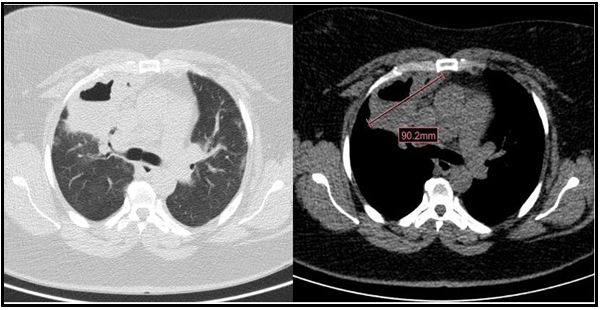

Lung cavitations in SARS-CoV-2 infection: A Case report